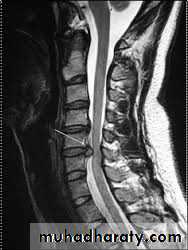

X-rays: show an abnormal narrowed disc space and to exclude bone diseases. After several attacks the disc space may be narrowed and small osteophytes appear.CT and MRI are more reliable than myelography.

CHRONIC INTERVERTEBRAL DISC DEGENERATIONMRI:

Bulging of the annulus fibrosus in both sagittal and axial projections and diminished thickness and reduced signal intensity (dehydration) of the degenerating disc.